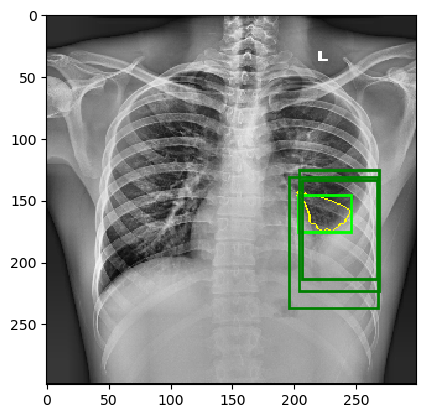

The behavior of MindfulLIME compared to LIME is demonstrated in Figures 4 and 5. Figure 4 showcases random sample 1 with a detected Pleural Effusion condition (annotations highlighted in green), while Figure 5 features random sample 2 with a detected Lung Opacity condition (annotations highlighted in blue). Each figure illustrates the disparities between the ground-truth annotations (darker-colored rectangles) and the generated explanations (lighter-colored rectangles surrounding the yellow border of the selected superpixels). We would like to emphasize that our trained classifier model generalizes well and is not simply memorizing the training data, as evidenced by its performance on a separate evaluation dataset.

The left columns depict the results for the top 1 feature, while the right columns display the results for the top 4 features. The first row presents the output of MindfulLIME, while the second and third rows represent the results of LIME using 1000 and 4000 samples, respectively. When comparing the results of LIME and MindfulLIME for two visual random samples, it becomes evident that MindfulLIME excels in multiple aspects. Firstly, MindfulLIME consistently identifies the top 1 feature with the highest similarity with the actual bounding box. Additionally, as the number of top features increases, MindfulLIME effectively prioritizes and presents more relevant features at the forefront. These findings highlight the enhanced performance and prioritization capabilities of MindfulLIME compared to LIME.